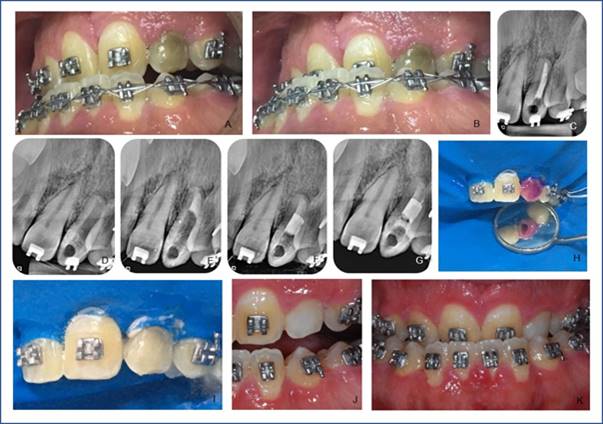

Clinical case 2 report: 30-year-old male with Apert syndrome attending HRAC/USP. He reports chromatic change in the lower left canine (22) (Fig. 2, A and B). This was verified on clinical examination, as well as the absence of painful symptoms. Unsatisfactory endodontic treatment was observed on the radiograph (Fig. 2, C). Endodontic retreatment (Fig. 2, D, and E) was performed. It was necessary to prepare an apical barrier with MTA (Fig. 2, F) (Angelus Ind. De Productos Odontológicos S/A, Londrina, PR, Brazil). Immediate internal tooth bleaching was started six months after retreatment. The color was recorded with the intraoral photo (Fig. 2, B) because the tooth color was not identified on the VITA scale (Wilcos do Brasil, Petrópolis, RJ, Brazil) as it was darker. Absolute insulation was then placed, followed by access to the pulp chamber using diamond bur No. 1012 (KG Sorensen Ind. Com. Ltda, Barueri, Brazil), endodontic obturation removal with No. 2 condensers, root canal entry. The cavity was cleaned, and the cervical barrier was prepared with SureFil SDR flow light-curing resin (Dentsply Ind. Com. Ltda, Petrópolis, RJ, Brazil) (Fig. 2, G). Acid etching of the pulp chamber was then performed with 37% phosphoric acid (Biodynamics, Ibiporã, PR, Brazil) for 30 seconds, then removed with plenty of water for 60 seconds and dried with an air jet. We handled 35% hydrogen peroxide gel (Whiteness HP, FGM, Joinville, SC, Brazil) following the manufacturer’s instructions and placed it inside the pulp chamber and on the buccal face (Fig. 2, H and I) with a medium-sized microbrush (KG Sorensen Ind. Com. Ltda, Barueri, Brazil) with a 45-minute application. The gel was removed after washing with water for 1 minute. A second application was performed for 25 minutes and sealed with SureFil SDR flow resin (Dentsply Ind. Com. Ltda, Petrópolis, RJ, Brazil). The second session included absolute isolation, cervical barrier with Top Dam (FGM, Joinville, SC, Brazil), acid etching, washing and drying in the same way, 35% hydrogen peroxide gel (Whiteness HP, FGM, Joinville, SC, Brazil) was handled following the manufacturer’s guidelines and inserted inside the pulp chamber and on the vestibular face with a medium-sized microbrush (KG Sorensen Ind. Com. Ltda, Barueri, Brazil). The first application lasted 15 minutes. After removing the gel, the second application was performed for 15 more minutes but only externally limited to the cervical region. Satisfactory results (Fig. 2, J and K) were achieved compared to the appearance before bleaching and temporary restoration with SureFil SDR flow resin (Dentsply Ind. Com. Ltda, Petrópolis, RJ, Brazil). On his return, the patient was referred to the Aesthetic Dentistry sector, where the final restoration was performed.